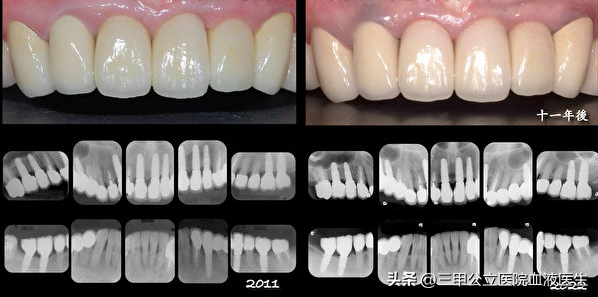

成功的種植牙有舒適美觀、穩(wěn)固牢靠、持久三大優(yōu)勢(shì),能修復(fù)恒牙缺失,重建咀嚼功能,提高人類生存質(zhì)量,因此種植牙被譽(yù)為“人類的第三副牙齒”